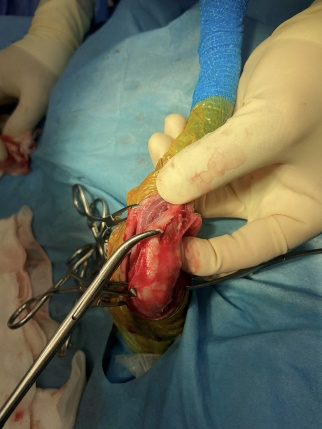

関節包縫合術

膝蓋骨が脱臼することにより緩んだ関節包の一部をメッツェンバーム剪刀で切除し、脱臼する前の状態に近づけます。これにより膝蓋骨が内側に緩みにくくなります。

内側支帯開放術

内側支帯筋の一部である縫工筋前部と内側広筋を関節包から分離し大腿直筋に縫合しています。これにより膝蓋骨を内側に引っ張る力が緩和されます。

脛骨粗面転移術

膝蓋靭帯の付着部である脛骨粗面を膝蓋骨が内側に脱線しない為にやや外側にずらします。この際脛骨粗面は全て切り落とすのではなく2mmほど脛骨につけたままに致します。